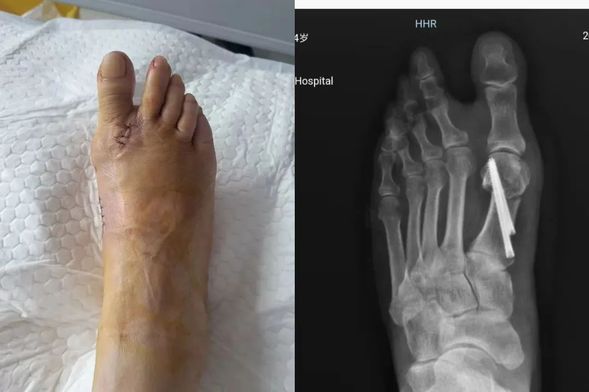

术后,创口小,恢复快

以往,传统拇外翻手术需要较大切口和复杂的内固定操作,术后恢复周期长,患者往往要承受较大痛苦,还可能面临二次手术取内固定的繁琐过程。而我院骨外四科引入的第三代微创拇外翻矫治技术,采用了微创小切口,相比第一代、第二代传统大切口接骨手术,大大降低了患者损伤,缩短了恢复时间,还降低了术后复发率。

术后第二日,已可穿前足免负重鞋正常下地行走

来到我院接受手术的患者大多是足拇趾外翻多年,随着年龄增长,外翻程度愈发严重,日常生活受到极大限制。在骨外四科主任邢星的带领下,医疗团队对每位患者进行了详尽的术前病情分析与讨论,经过周密检查,最终决定采用第三代微创拇外翻技术为他们进行治疗。在麻醉科与手术室的紧密配合下,手术顺利完成。术后,患者患足外观恢复良好,效果令人满意。